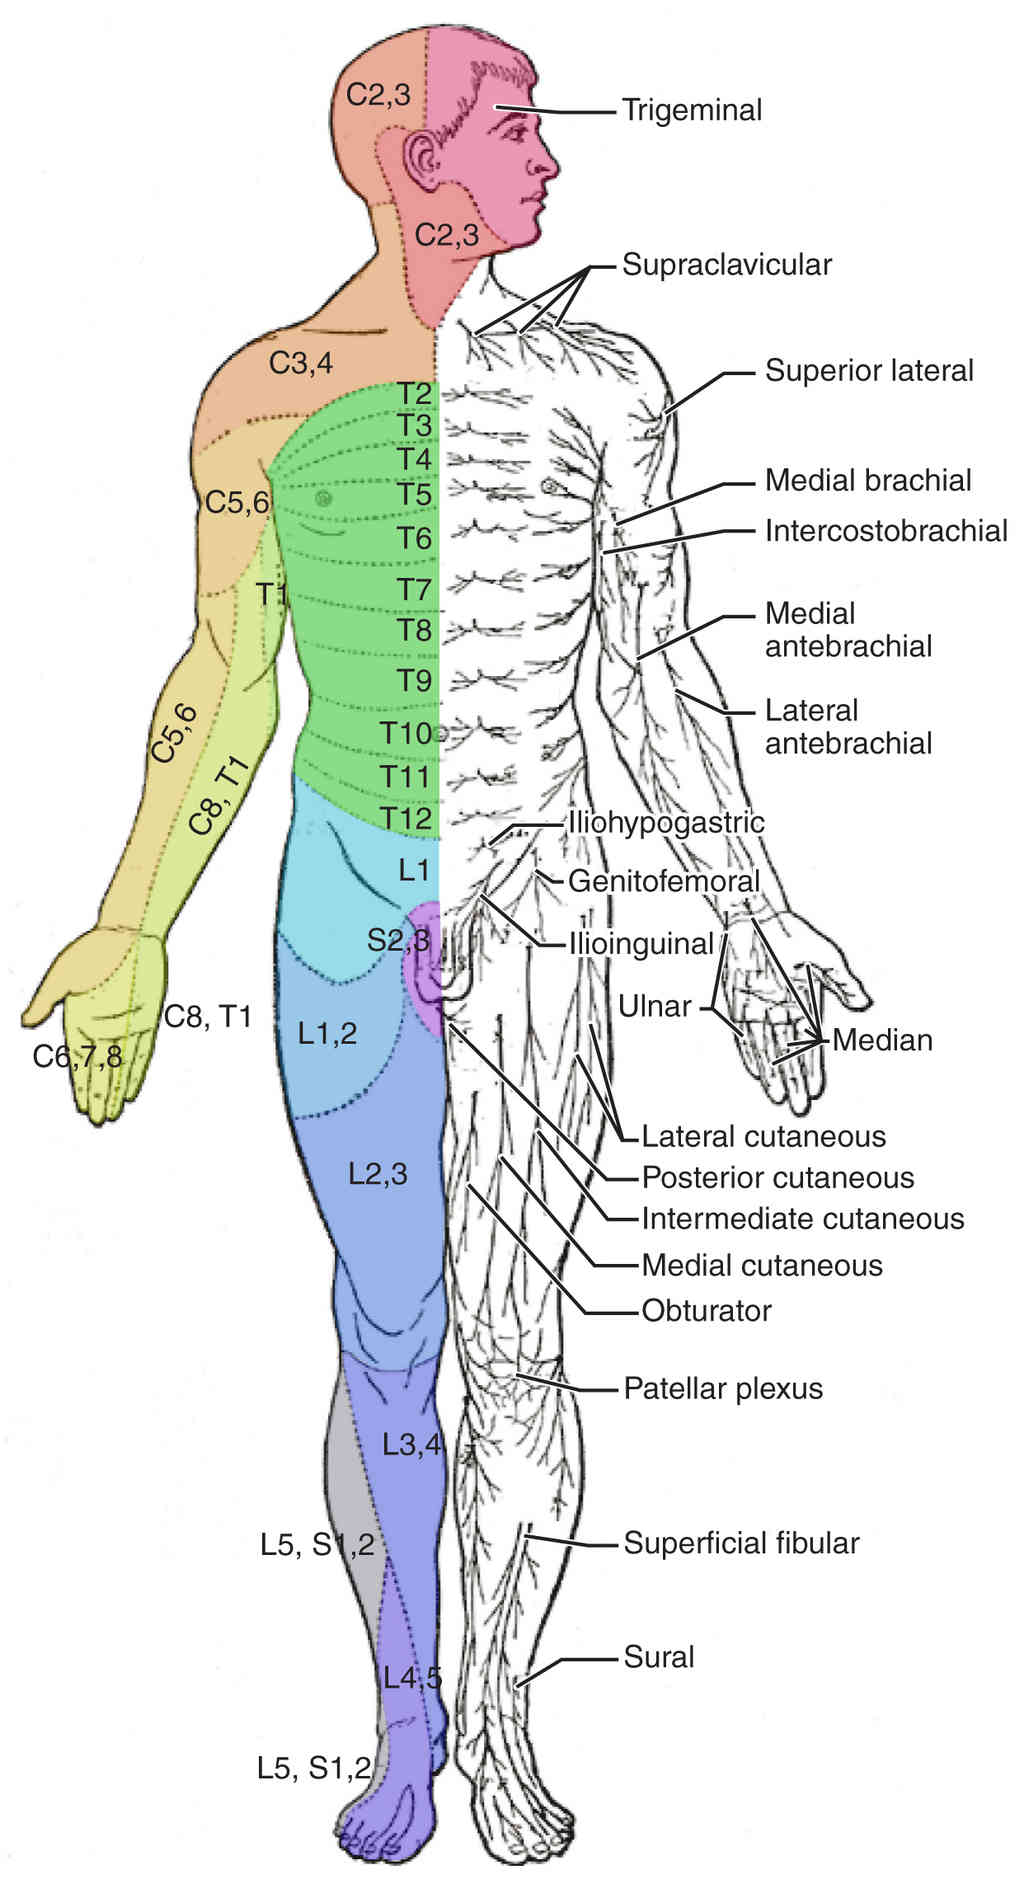

This page is under construction. For now, it is just a resource of the images found in the OpenStax Anatomy and Physiology Handbook. It wil slowly change into a revision tool. Each slide has a number. Use this to refer to the slide. When completed, it will have an unlabelled section, with labelled slides in parallel. On the unlabelled slides, write your answer and use the labelled slide to assess yourself. Keep track by also noting the number on each slide. Improvement at each attempt is important, more so than full marks on a first attempt.